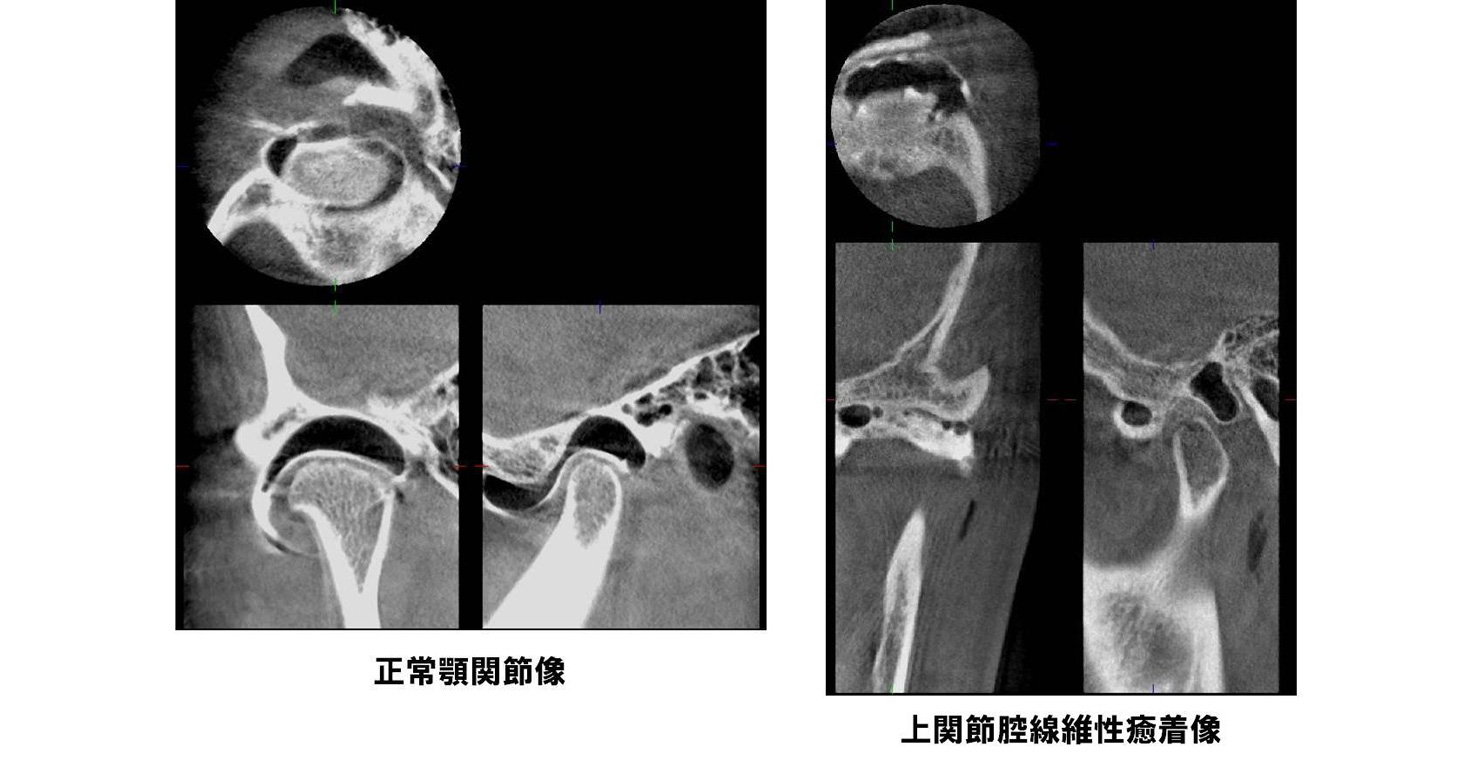

| 機能障害 | 顎関節症(注2)(注3)、顎関節強直症、顎変形症など(注2)[顎関節症] 顎関節症とは口を開けると顎の関節にカクカク音がする、顎の関節が痛い、口が開かない、顎がだるい、肩こりや頭痛がする、といった症状があり、関節雑音、開口障害、咀嚼障害を呈する疾患です。 顎関節症は正しく診断・治療すればそのほとんどが軽快しますが放置しておくと経時的に変形性関節症にまで悪化することが知られています。 当科では顎関節造影検査、関節腔内洗浄療法、スプリント療法(いずれも予約制)などの顎関節症専門外来を行っております。 |

(注2)[顎関節症]

顎関節症とは口を開けると顎の関節にカクカク音がする、顎の関節が痛い、口が開かない、顎がだるい、肩こりや頭痛がする、といった症状があり、関節雑音、開口障害、咀嚼障害を呈する疾患です。

顎関節症は正しく診断・治療すればそのほとんどが軽快しますが放置しておくと経時的に変形性関節症にまで悪化することが知られています。

当科では顎関節造影検査、関節腔内洗浄療法、スプリント療法(いずれも予約制)などの顎関節症専門外来を行っております。

当科では2008年3月よりベラビューエポックスを導入しました。この装置はパノラマ画像と3次元的歯科用CT画像が低照射量、短時間で撮影できます。歯の根尖病巣や顎骨病変、顎関節造影検査での診断やインプラント、抜歯などの術前精査において有効に用いられています。